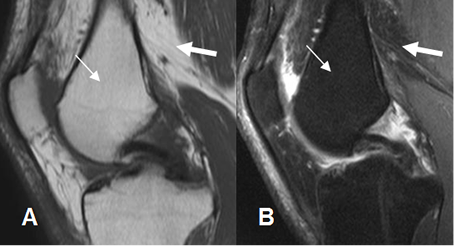

Fig 3. Medula ósea en adulto normal

A: RM sagital en T1 y B: RM sagital en STIR. La señal de la medula osea amarilla (Flecha delgada), es similar a la de la grasa (Flecha gruesa).